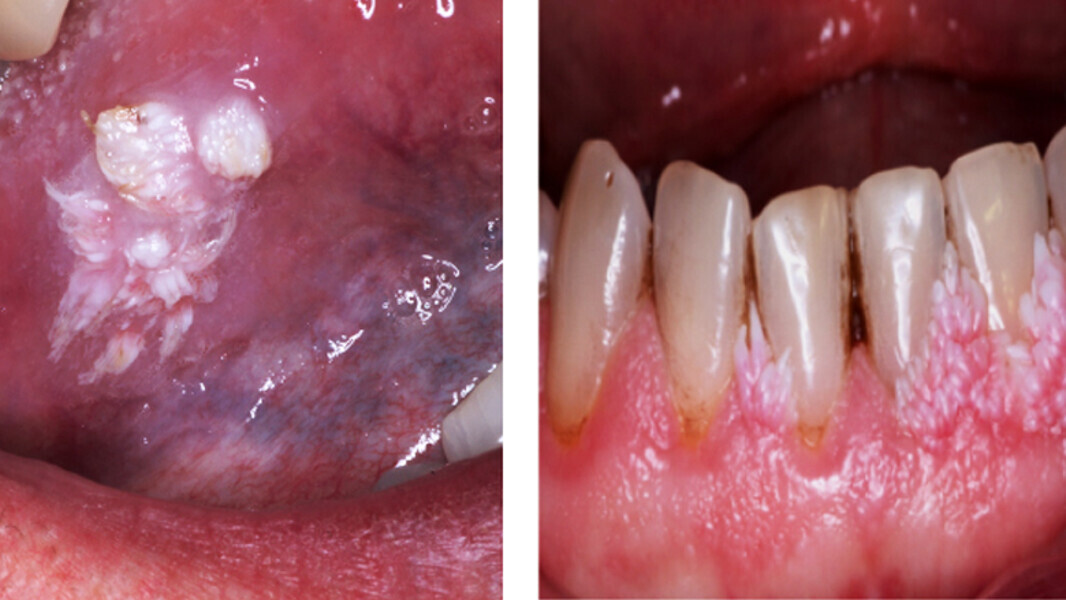

Fig. 6. Verrugas y condilomas. Los pacientes con SIDA suelen presentar múltiples lesiones de VPH en mucosa genital y bucal, asociadas a inmunosupresión.